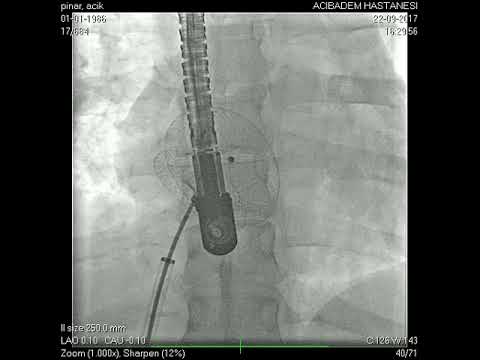

Anjiyografik İşlemler

Kapat